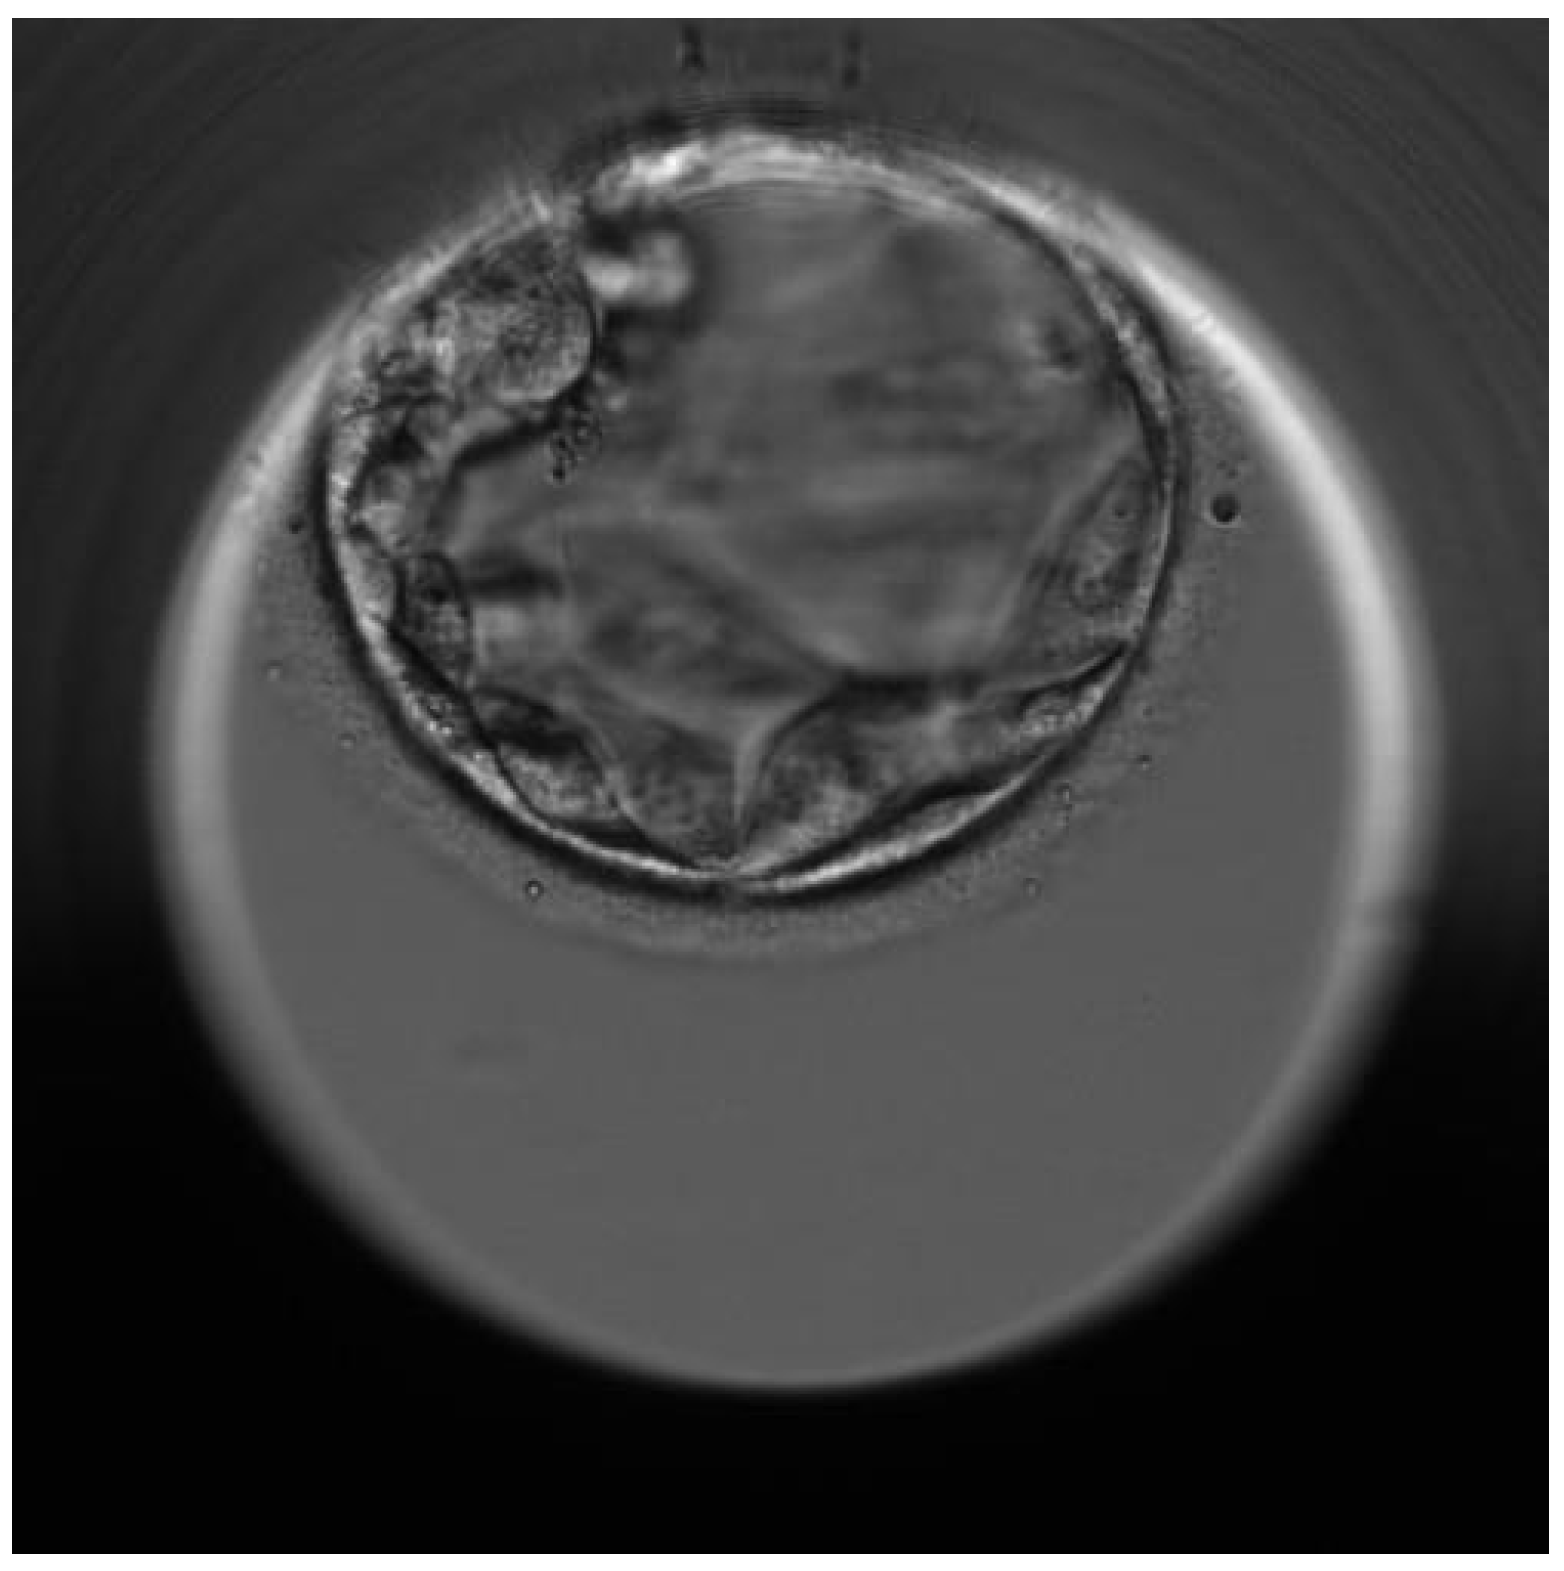

| First euploid embryo (W3) | Healthy embryo | Carrier of the mother’s mutation |

| Second euploid embryo (W4) | Healthy embryo | Healthy embryo (Wild-type) for both mutations |